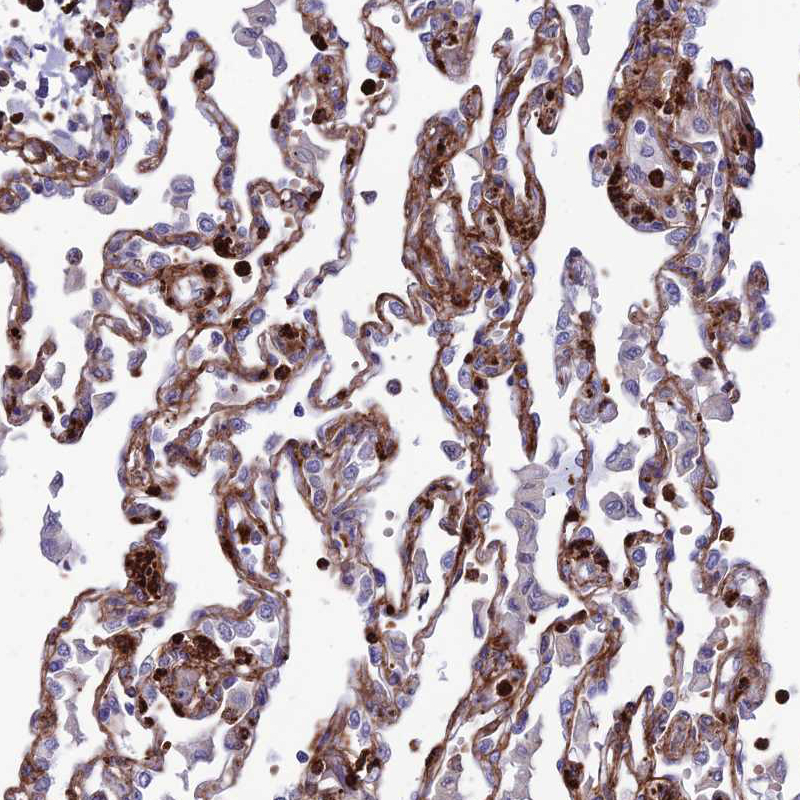

Immunohistochemical staining of human lung shows moderate to strong membranous positivity in pneumocytes.